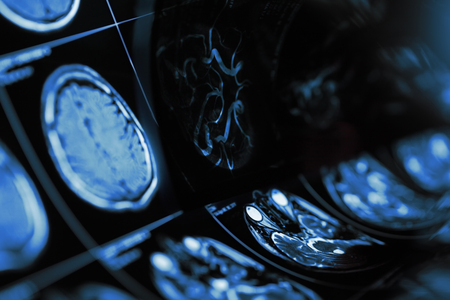

Close up of advanced mri equipment in a medical office analyzing brain scans and human health

Magnetic resonance imaging of human brain with suspected cerebropathy.

closeup series of MRI images of head and brain, magnetic resonance imaging scan, world cancer day concept